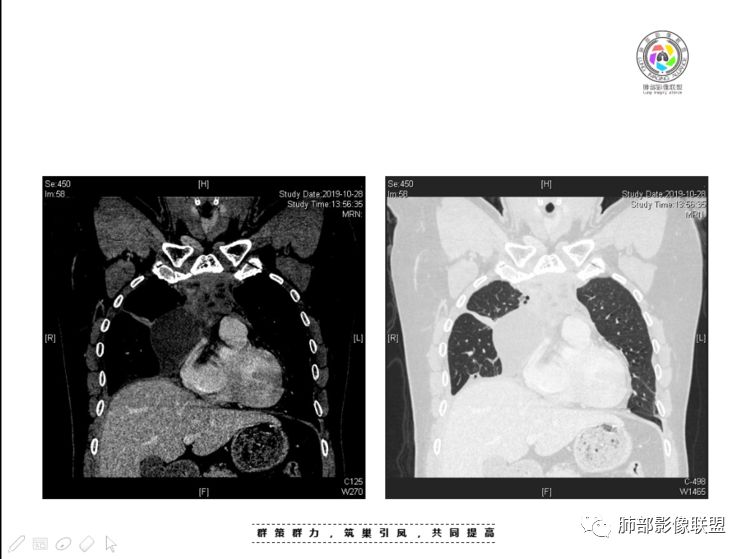

2、前纵隔内病灶囊实性混杂密度病灶,囊性病灶主要位于右侧,张力较高,有分隔影,囊壁右侧缘光整,病灶左侧实性部分边界不清明显强化,病灶肺瘤交界面大部分边界清楚,部分模糊。

前纵隔肿块伴囊变坏死常见以有胸腺瘤、胸腺癌、淋巴瘤和生殖细胞肿瘤。

纵隔内病灶不符合肺癌转移途径,且纵隔内单发的囊实性转移罕见。淋巴瘤无论是分布、形态、密度、还是强化方式度不符合。

胸腺瘤/胸腺癌符合吗?

胸腺瘤/胸腺癌:病灶内那么大的囊,常规考虑B型以上胸腺瘤,囊内有分隔影,病灶周围脂肪间隙模糊,常规考虑侵袭性胸腺瘤或胸腺癌,若侵袭性胸腺瘤,常侵犯胸膜、心包,很少累及肺。胸腺癌易侵犯胸膜、肺并纵隔淋巴结及远处转移。但肺内腺癌形态更符合原发灶。胸膜及叶间裂转移则即可来自肺,也可来自胸腺癌。

尽管前纵隔病灶缺乏相关病理资料,但是小编还是认为肺内与纵隔病灶以二元论解释。只是肺内恶性病灶引发的胸膜改变可能会影响我们对纵隔病灶的判断。